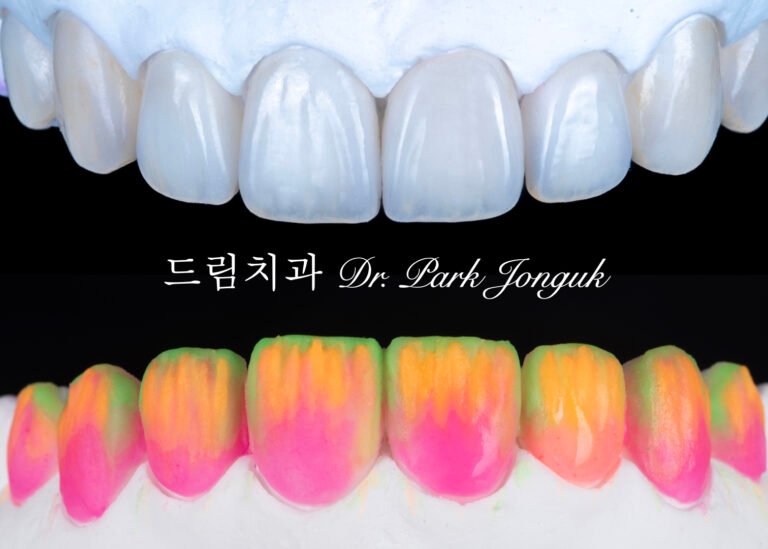

라미네이트와 올세라믹 크라운 재시술: 불투명하고 어색한 치아를 자연스럽게

투명감 있는 라미네이트 vs 불투명한 라미네이트: 빌드업과 원데이 제작 방식의 질적 차이